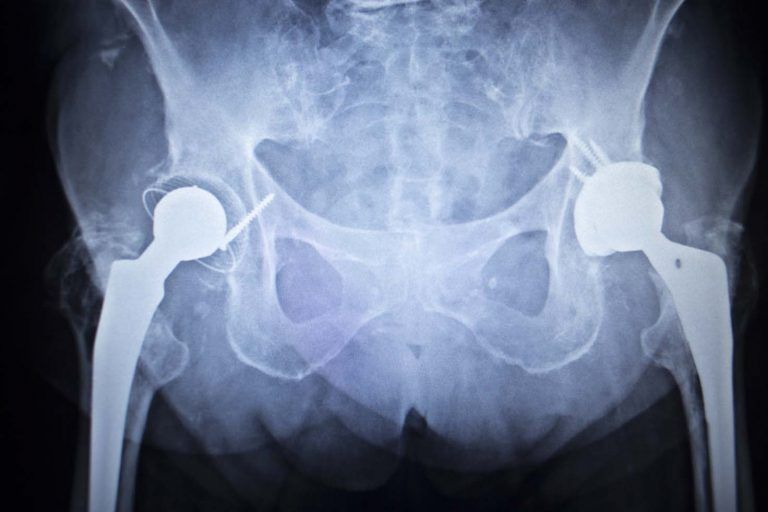

It is estimated that over 500,000 people received metal-on-metal hip implants over the last 10 years in the U.S. alone. The dangers associated with these devices—which fail at an alarming rate—are well documented.

The metal-on-metal movement inside the human body can cause the release of tiny metal particles. This can damage the surrounding soft tissue and bone. It may even enter the bloodstream causing other systemic health issues. Failure often requires revision surgery to remove or replace the implant.

The sky-high failure rates of metal-on-metal hip implants are evidenced by the number of revision surgeries and thousands of lawsuits brought by injured plaintiffs. There are two types of metal-on-metal hip implants: